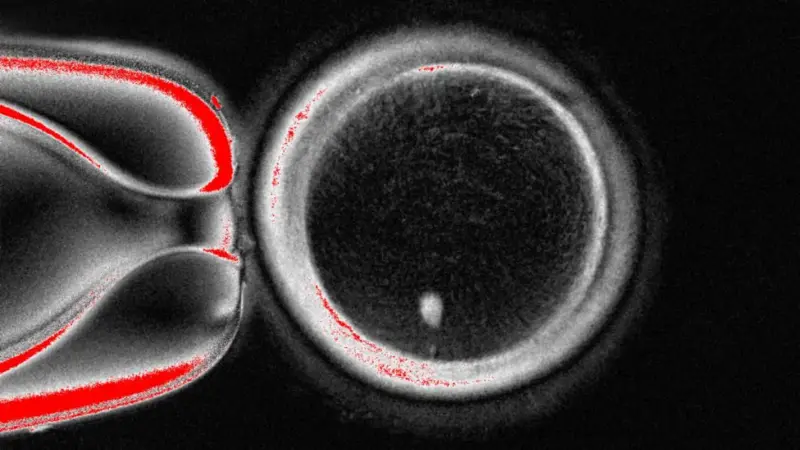

Cientistas americanos produziram, pela primeira vez, embriões humanos em estágio inicial, manipulando DNA retirado das células da pele de pessoas, fertilizadas com espermatozoides.

A técnica criada pela equipe de pesquisa da Universidade de Ciências e Saúde de Oregon, nos Estados Unidos, retira o núcleo de uma célula da pele.

Este núcleo contém uma cópia de todo o código genético necessário para a construção do corpo humano. Ele é colocado no interior de um óvulo doador, que teve suas instruções genéticas retiradas.

Mas este óvulo não está pronto para ser fertilizado pelo espermatozoide, pois ele já contém um conjunto completo de cromossomos. De cada um dos nossos pais, nós herdamos 23 conjuntos de DNA. O total é de 46, que já estão contidos no óvulo formado.

A próxima etapa é convencer o óvulo a descartar metade dos seus cromossomos. Os pesquisadores chamam este processo de “mitomeiose” — uma fusão dos termos “mitose” e “meiose”, que são as duas formas de divisão celular.

O estudo foi publicado na revista Nature Communications e mostra que foram produzidos 82 óvulos funcionais.

Eles foram fertilizados com espermatozoides e alguns deles progrediram para os estágios iniciais de desenvolvimento de embriões. Nenhum deles se desenvolveu além do estágio de seis dias.